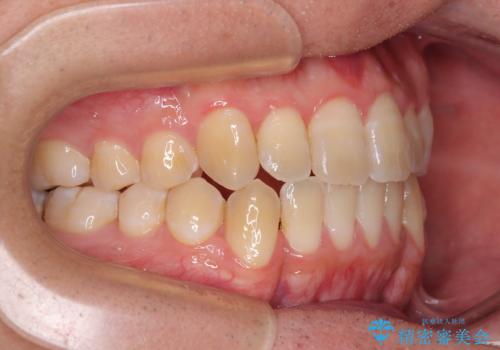

オープンバイトをインビザラインで矯正治療

開咬の治療は、前歯を閉じるように動かすとともに、上下臼歯を圧下(骨内にめり込ませる)させることで進めて行きます。

インビザラインは臼歯の圧下を効果的に行えるため、インビザラインを用いて矯正治療を行うこととしました。

オープンバイトは舌の突出癖により誘発され、治療後も突出癖が残っている容易に後戻りしてしまいます。

治療期間を短縮するためにも、舌突出癖の改善が極めて重要となります。